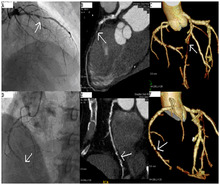

A coronary angiogram (an X-ray with radiocontrast agent in the coronary arteries) that shows the left coronary circulation. The distal left main coronary artery (LMCA) is in the left upper quadrant of the image. Its main branches (also visible) are the left circumflex artery (LCX), which courses top-to-bottom initially and then toward the centre/bottom, and the left anterior descending (LAD) artery, which courses from left-to-right on the image and then down the middle of the image to project underneath the distal LCX. The LAD, as is usual, has two large diagonal branches, which arise at the centre-top of the image and course toward the centre/right of the image.